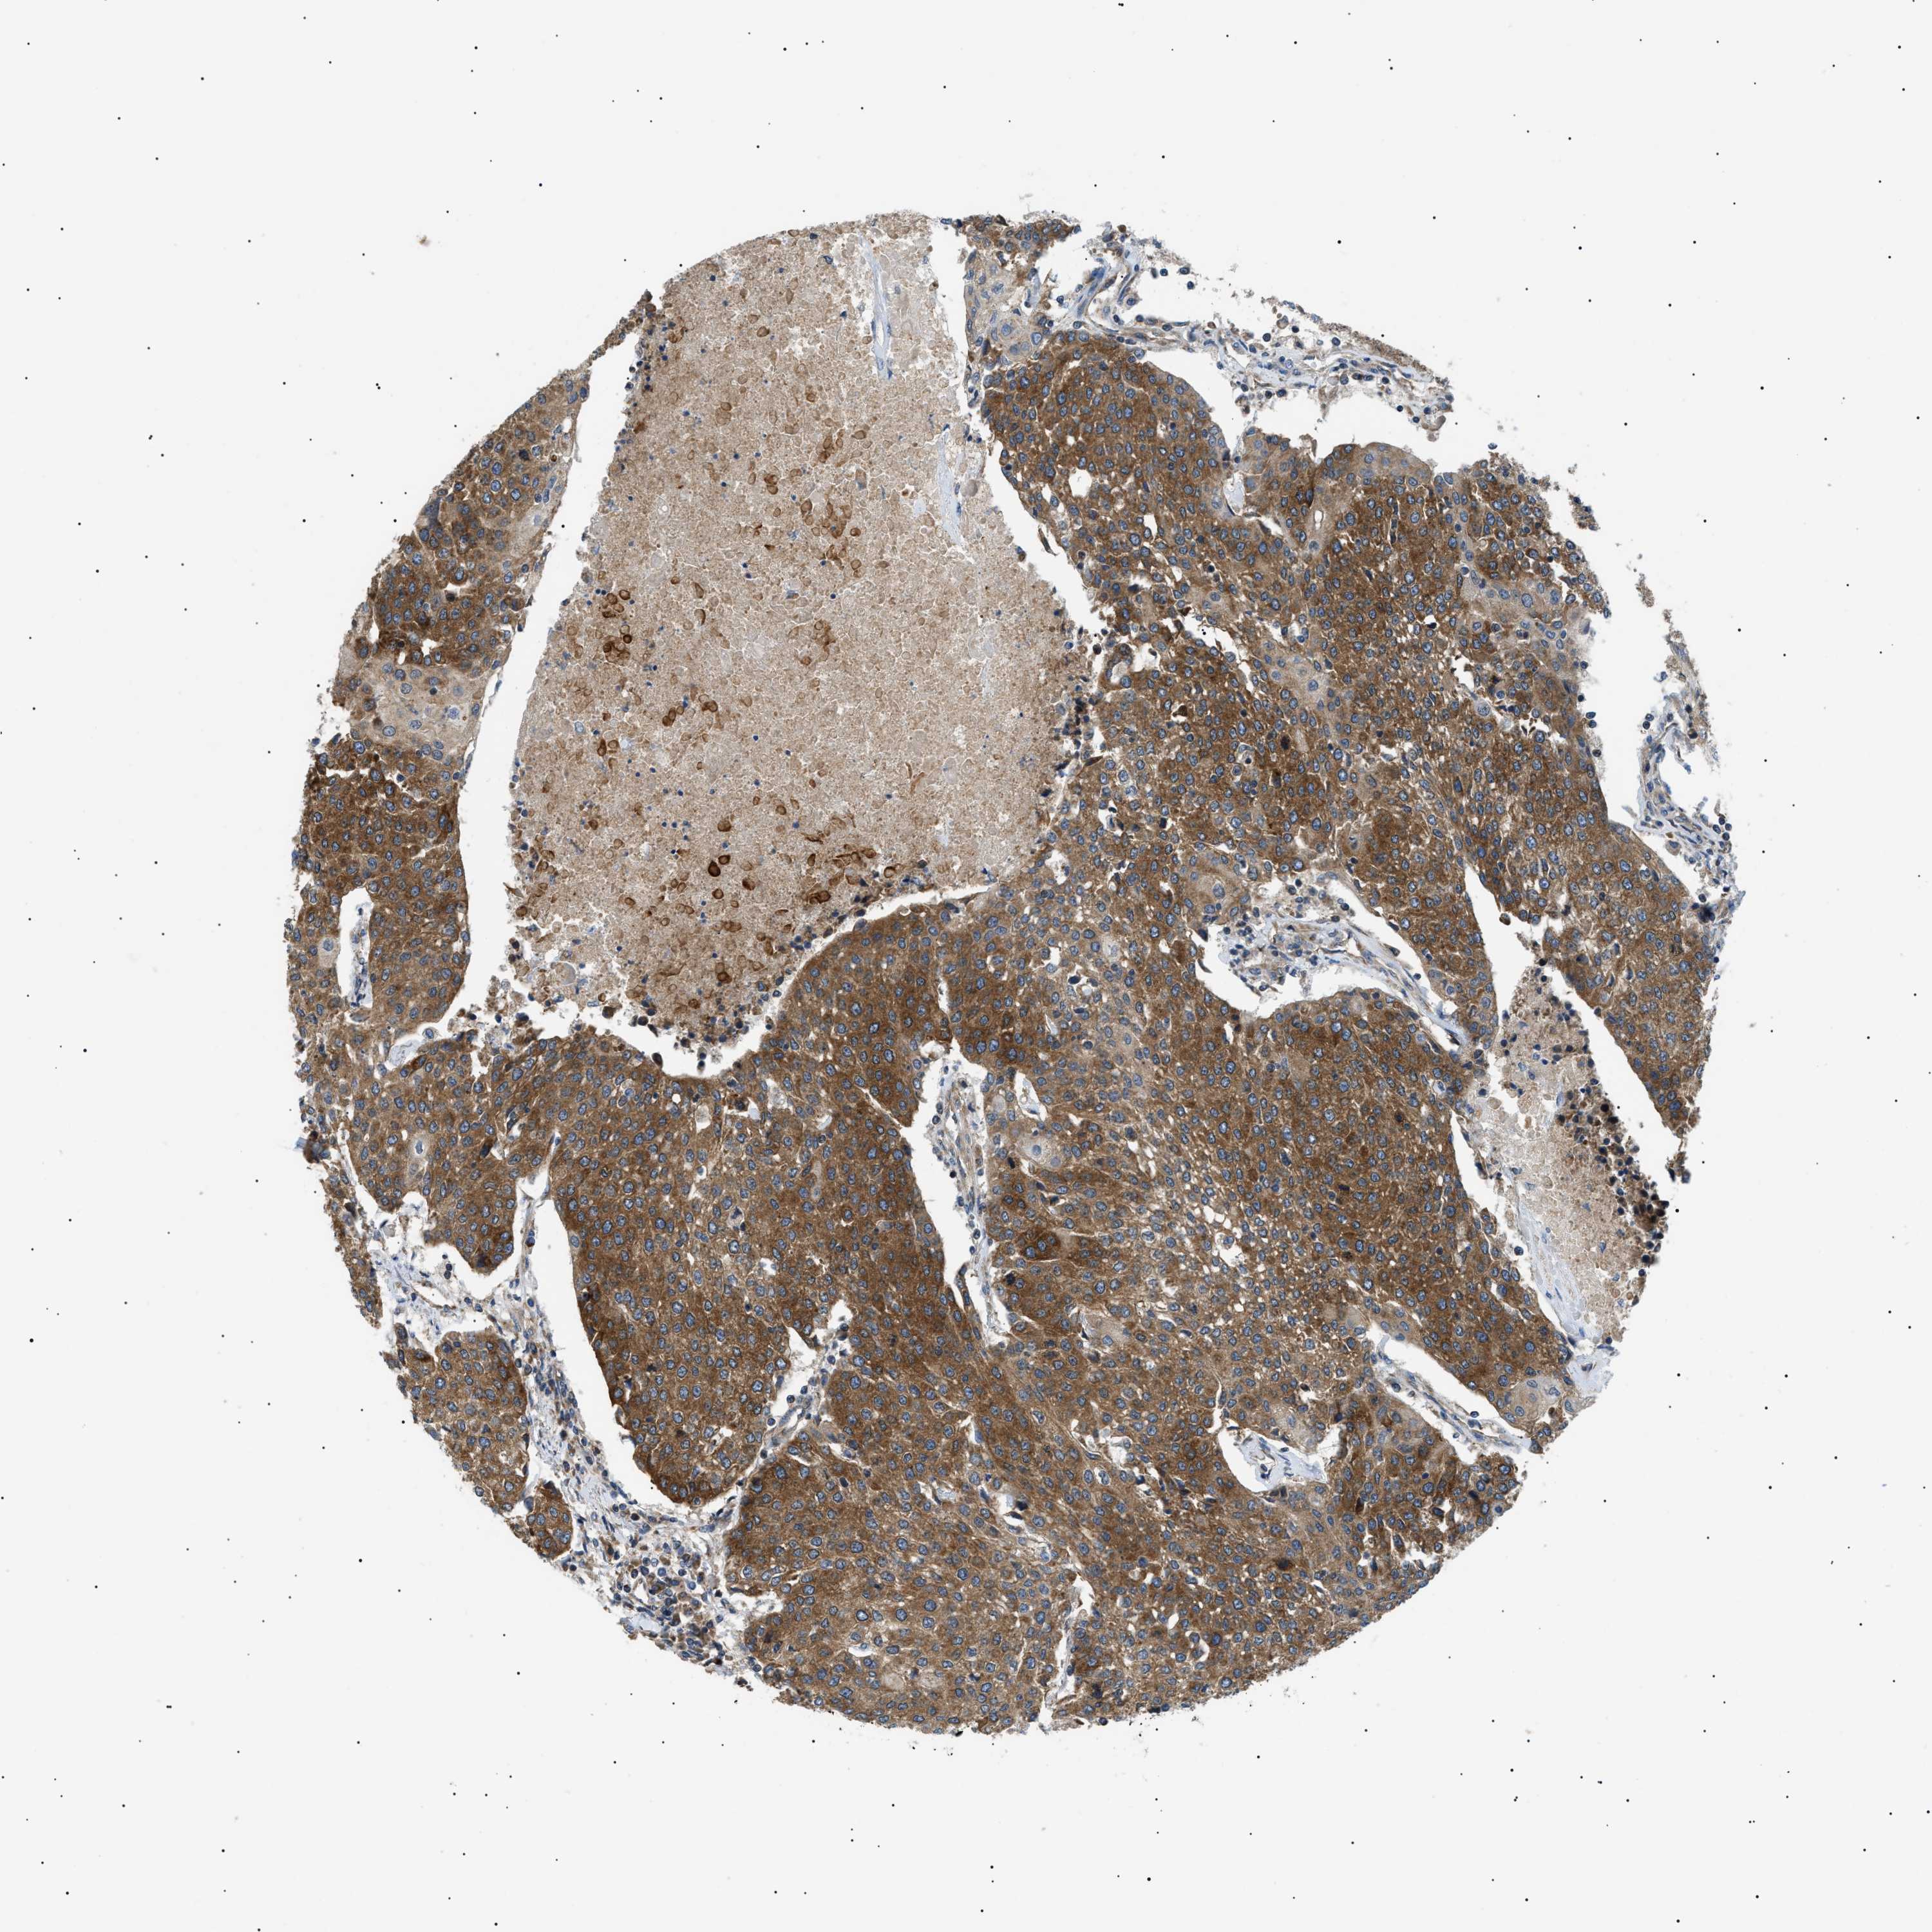

UROTHELIAL CANCER - Protein expressioni

A mouse-over function shows sample information and annotation data. Click on an image to view it in a full screen mode. Samples can be filtered based on level of antibody staining by selecting one or several of the following categories: high, medium, low and not detected. The assay and annotation is described here.

Note that samples used for immunohistochemistry by the Human Protein Atlas do not correspond to samples in the TCGA dataset.

Antibody stainingi

Antibody staining in the annotated cell types in the current human tissue is reported as not detected, low, medium, or high, based on conventional immunohistochemistry profiling in selected tissues. This score is based on the combination of the staining intensity and fraction of stained cells.

Each image is clickable and will lead to virtual microscopy that enables deeper exploration of all samples and also displays staining intensity scores, fraction scores and subcellular localization as well as patient and tissue information for each sample.

Antibody HPA016431

Staining

High

Medium

Low

Not detected

Intensity

Strong

Moderate

Weak

Negative

Quantity

>75%

75%-25%

<25%

None

Location

Nuclear

Cytoplasmic/membranous

Cytoplasmic/membranous,nuclear

Urothelial carcinoma, Low grade

Urothelial carcinoma, High grade